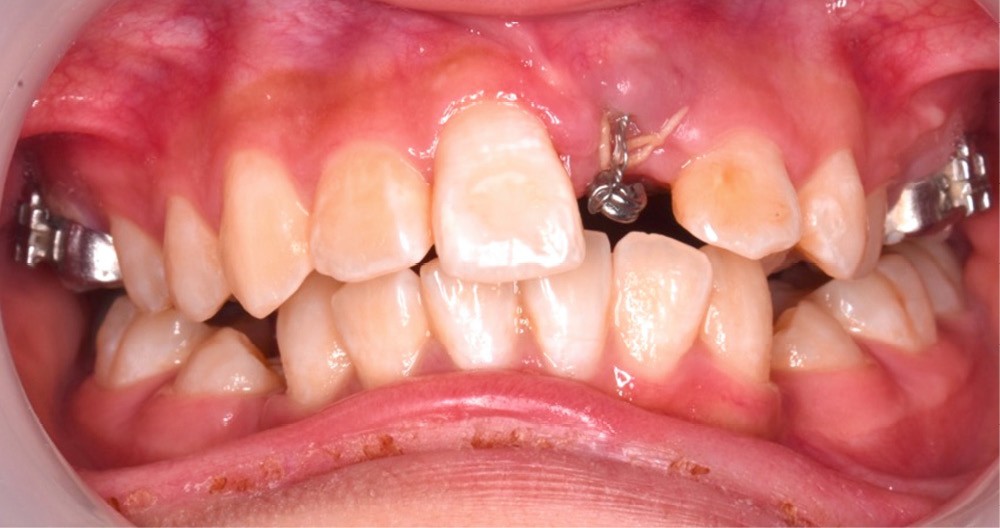

L’objectif du traitement est la correction de la DDA tout en assurant le remplacement de la 21 compromise. Décision a été prise d’extraire 34 et 44, ainsi que 21 et 14. La traction de la 23 a été réalisée à l’aide de forces légères, sur un arc transpalatin (fig. 9). Le nivellement et l’alignement, puis une mécanique par glissement ont permis d’aménager l’espace suffisant à la stratification de la canine. Elle associait un ressort en nickel-titane à des élastiques de Classe II (4 ½ oz, 3/16’’) sur un arc en acier .019×.025. Une phase d’ingression a été réalisée pour ajuster le niveau du bord libre de la canine à celui de l’incisive controlatérale (fig. 10-12).